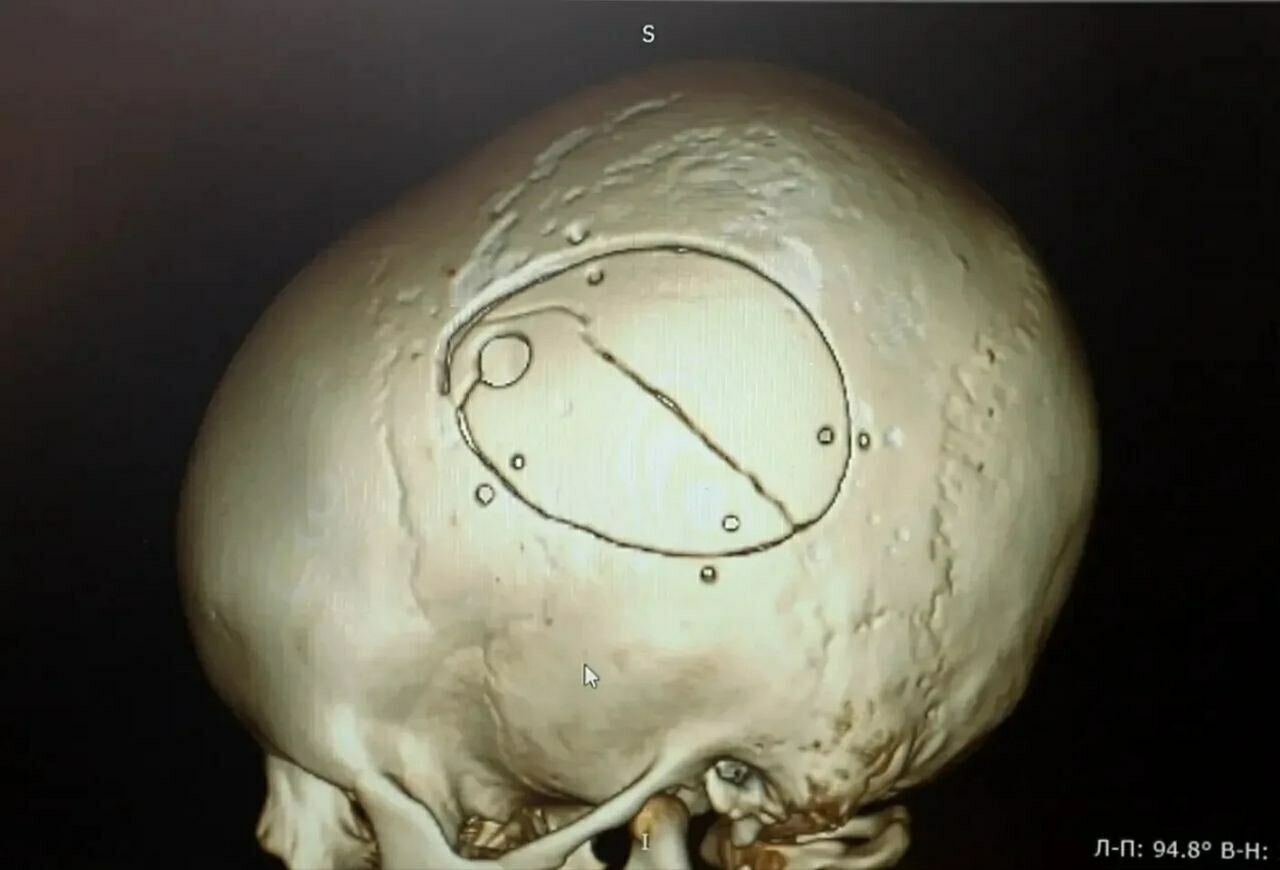

Мальчика экстренно доставили в операционную. Нейрохирурги провели сложную операцию – костно-пластическую трепанацию черепа, удалили гематому и остановили кровотечение.